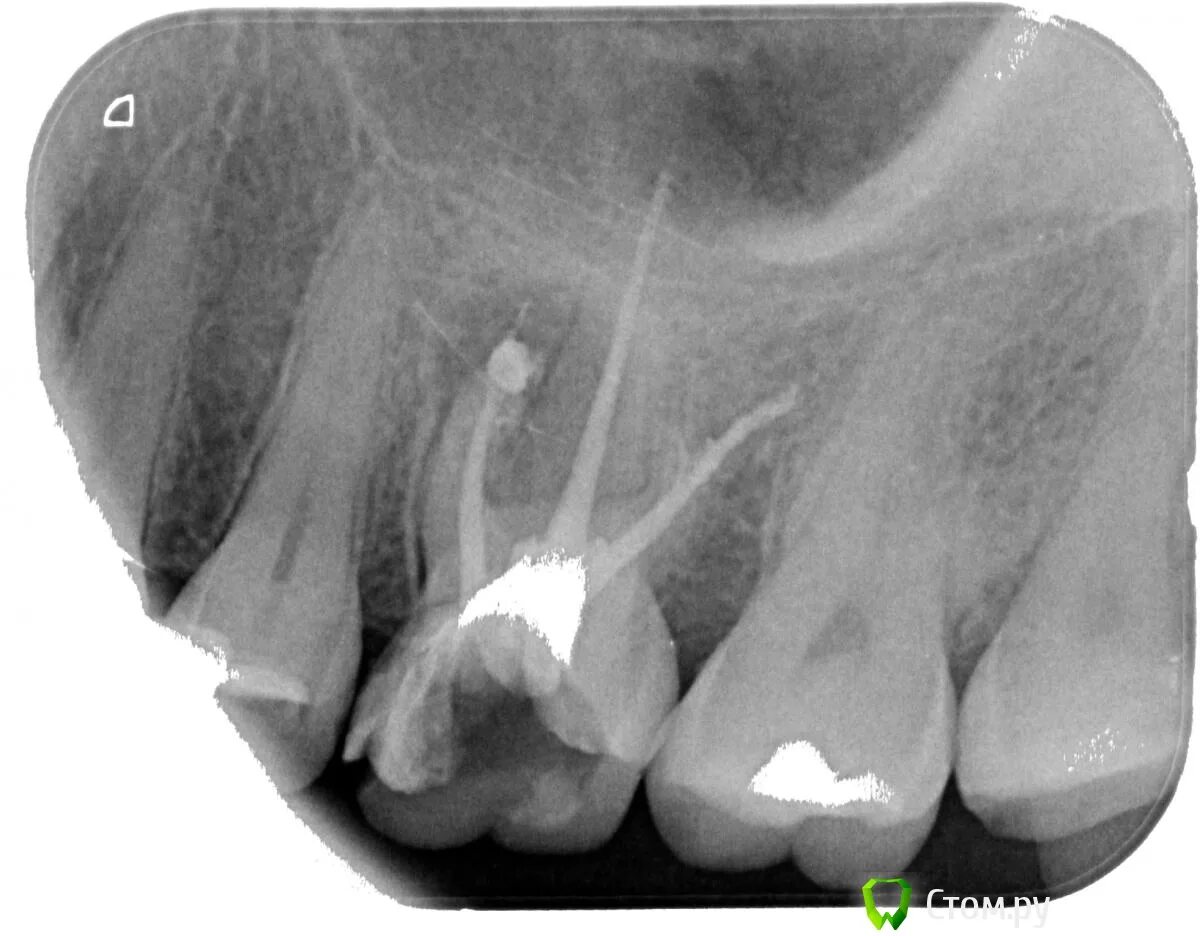

Обтурация корневого канала рентген. пульпит 17 зуба рентген с запломбированными каналами. пломбировка каналов зуба рентген.

17 зуб анатомия корневых каналов. каналы 46 зуба анатомия корневые. 24 зуб анатомия корневых каналов. анатомия корневых каналов 37 зуба.